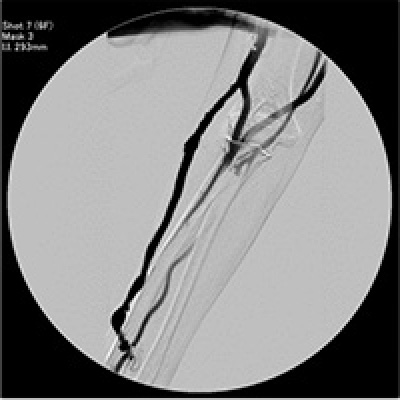

左の写真はPTA前の造影検査の写真です。黒く写っているのが、シャントになります。真ん中の写真では、狭い部分に対し、バルーン(風船)を膨らませて、血管を広げています。右の写真はPTA後の造影検査の写真です。

放射線を用いる場合は「手技が容易であり、再現性に優れ、治療中の血管破裂などのリスクが少ない」「シャント全体の評価が容易」などのメリットはありますが、「造影剤を使用するために、喘息などのアレルギーがある患者様には使用ができない」「放射線による被ばくの恐れ」があるなどのデメリットがあります。

放射線による被ばくは「放射線を使用する時間をできるだけ短くする」「放射線を使用する範囲を小さくする」「防護具を付ける」などによって、被ばく量を減らすようにしています。

超音波を用いる場合は「放射線被ばくがない」「アレルギーのある患者様にも使用できる」などのメリットはありますが、「手技が難しく、再現性が得られにくいために治療評価が難しい(=患者様も理解しにくい)」「出血など合併症に対応するのが遅れる可能性がある」「鎖骨下などの中心静脈の評価ができない」などのデメリットがあります。

それぞれ一長一短ですので、それぞれの状況に応じて対応することとしています。